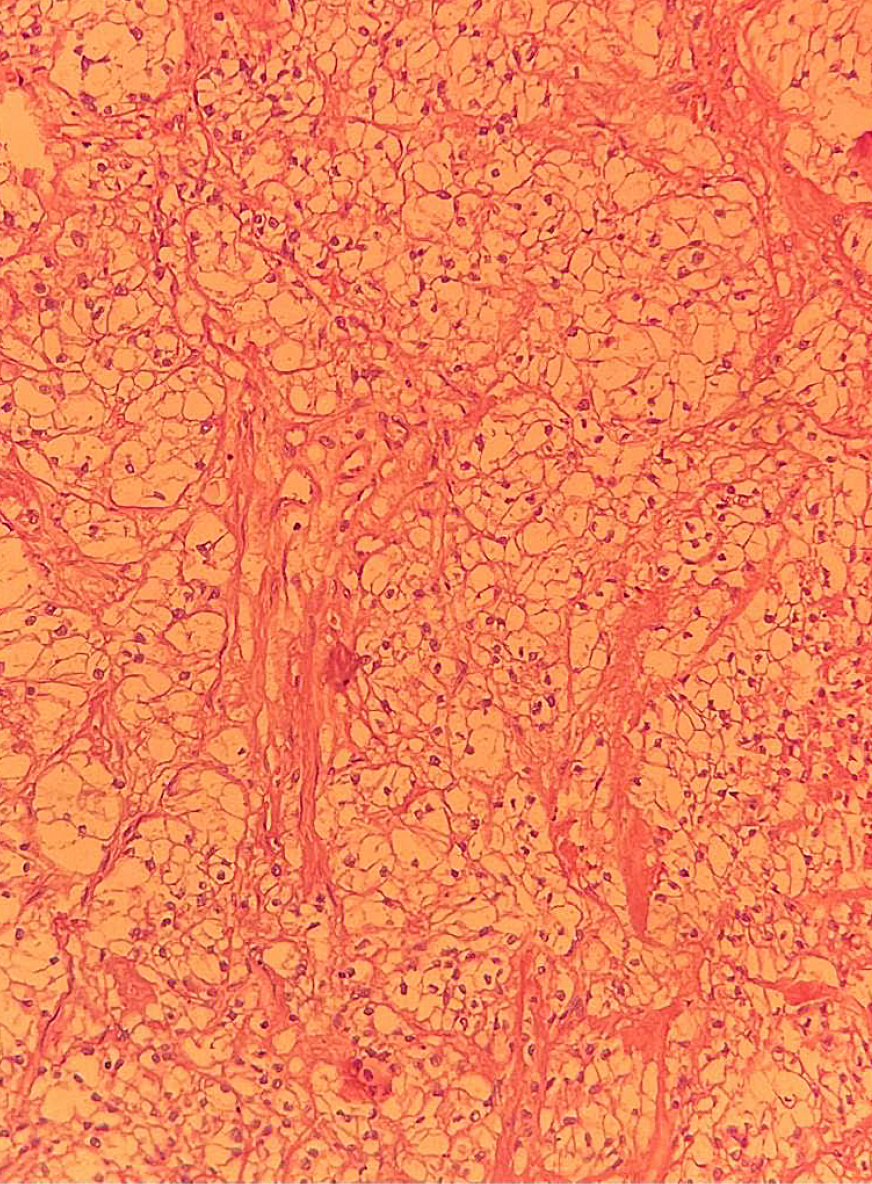

Histological examination revealed metastases of light renal cell carcinoma in the pancreatic head, spreading into the duodenal wall to the mucous layer, with ulceration. Metastases also were found in 4 peripancreatic lymph nodes, as well as in the body and tail of the pancreas (Fig. 1)

Fig.1. Сells of clear cell squamuos cell carcinoma of the right kidney. Stained with hematoxylin and eosin х100